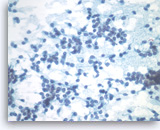

Pancreatic endocrine neoplasm #1,

Pancreas FNA, Cell Block.

The synaptophysin immunostain shows cytoplasmic positivity in the tumor cells, indicative of neuroendocrine differentiation.

40X